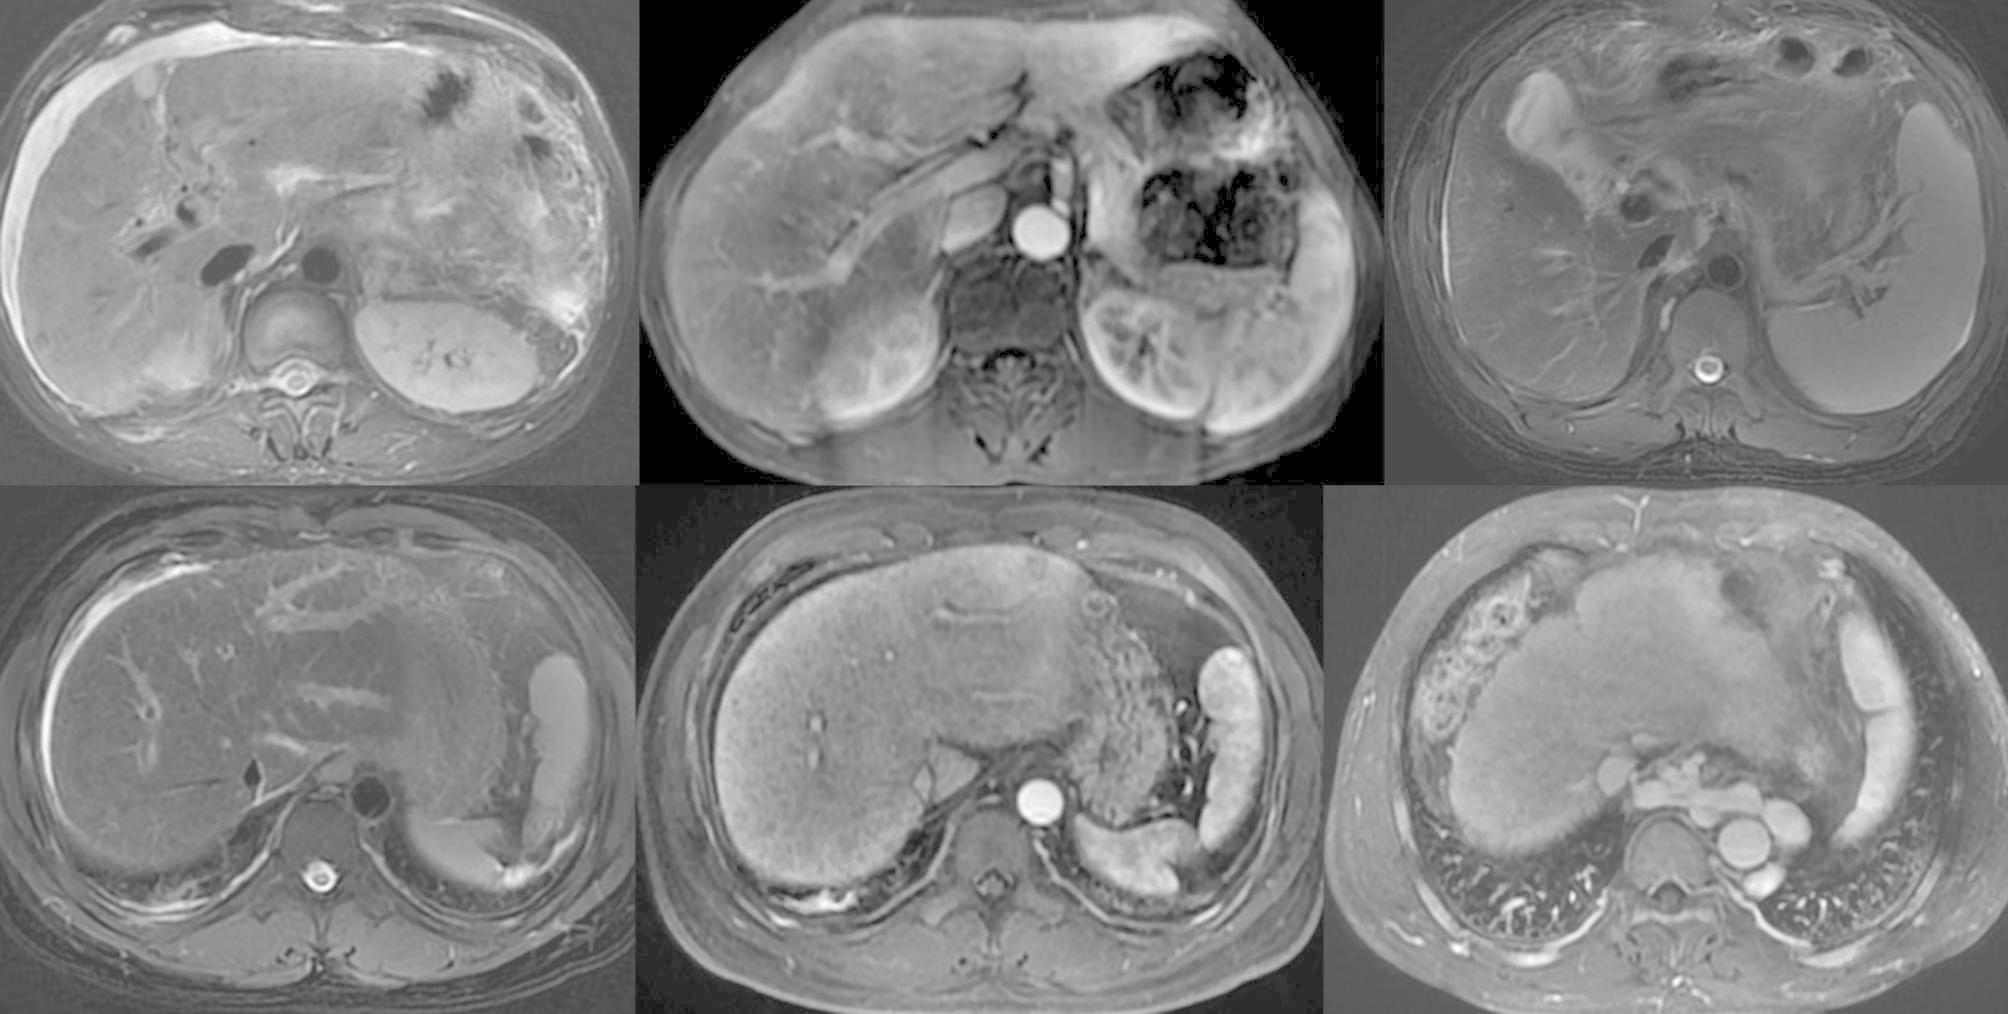

Two radiologists with 15 and 5 years of experience in abdominal imaging reviewed and discussed the MR images in consensus. The MR imaging features of ACLF were evaluated based on previous imaging studies and clinical experience [17–19, 22], which included (a) diffuse hyperintense of the liver on T2WI, (b) patchy enhancement of the liver at the arterial phase, (c) uneven enhancement of the liver at the portal vein phase, (d) gallbladder wall edema, (e) periportal edema, (f) ascites, (g) esophageal varix, (h) gastric varix, (i) umbilical vein patefac, (j) portal vein thrombosis, and (k) splenomegaly (Fig. 2). Gallbladder wall edema was defined as hyperintensity on T2WI between the inner and outer walls. Periportal edema was defined as hyperintense tramlines or rings surrounding the portal vein and branches on T2WI or low intensity tramlines or rings around the portal vein and branches at PVP. Ascites were classified into mild, moderate, and severe according to the amount [23].

Fig. 2.

MR imaging features of ACLF. (a) Diffuse hyperintense of the liver on T2WI and ascites in patients with decompensated cirrhosis; (b) patchy enhancement of the liver mainly located in the left lobe at the arterial phase in patients with chronic hepatitis B; (c) gallbladder wall thickening on T2WI in patients with compensated cirrhosis; (d) and (e) periportal edema, (d) hyperintense tramlines or rings around the flow void in the segmental portal vein in patients with chronic hepatitis B on T2WI and (e) low intensity at corresponding locations at the PVP; and (f) gastric varix in patients with decompensated cirrhosis at the PVP.